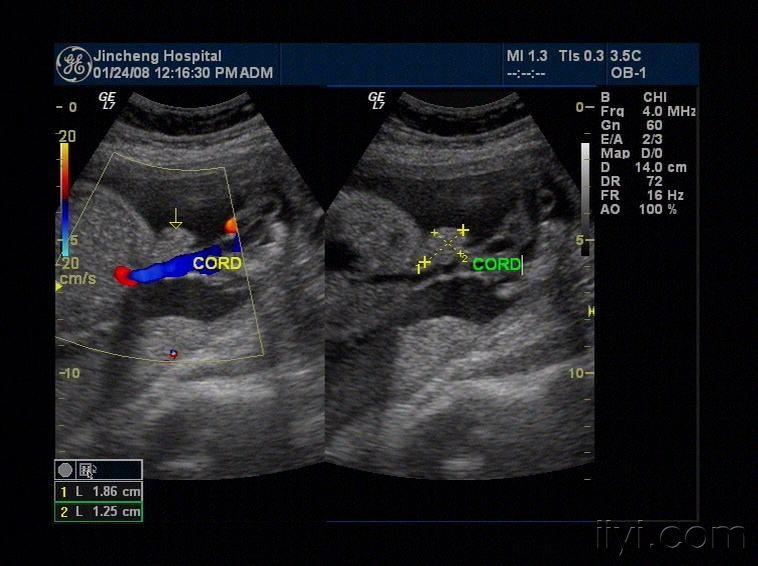

13周孕胎儿单脐带动脉声像图

单脐动脉